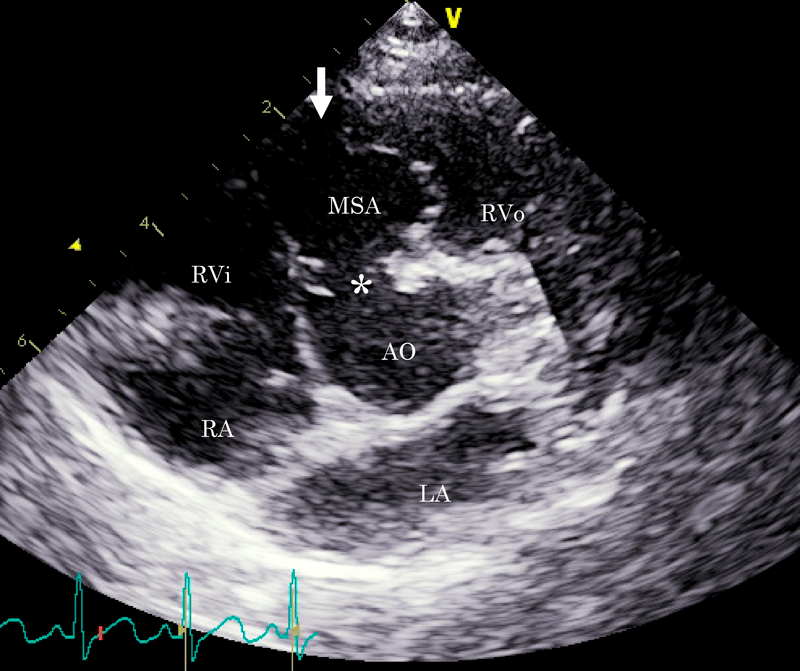

膜様部中隔瘤による右室流出路狭窄を呈した心室中隔欠損の一例Right Ventricular Outflow Obstruction by a Membranous Septal Aneurysm in a Ventricular Septal Defect